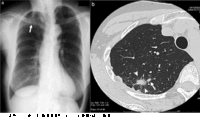

肺炎の時にレントゲンを撮ると、 肺に白い影が映ります。 マイコプラズマ肺炎の場合は、スリガラス様陰影が特徴で、肺血管陰影が透かして見える程淡く白い陰影を表します。 詳細は、画像をご覧下さい。 マイコプラズマ肺炎と正常な肺の比較画像 健康診断の基本編の1項目でもある胸部x線検査 についてです。 胸部レントゲン検査 は肺・心臓・大動脈など呼吸器と循環器異常がないか調べる検査でよく行われています。検査結果の見方や検査当日の注意事項、服装や検査前の食事の取り方など紹介して行きます。第1章 胸部x線写真の正しい理解と読影 4 jcopy c.肺野の観察法 1)肺野の病変を見落とさないためのコツ 肺野は,肺門部を除く肺末梢の領域をさす.肺野の異常は,正常部より透過性が亢進

医療機関でもレントゲン車でも、一般的な健康診断であれば同じレベルの写真を撮ることができます。 デジタル式撮影によってより安全に X線は光の一種で、物質を通り抜けることで体の中を映し出します。X線が通り抜けにくいものが、影として白っぽく写ります。 X線も放射線であること大動脈弓が、正常な場合とは逆に右後方に向かい、脊椎の右側を下降しています。生まれつきの異常によるものです。 横隔膜の挙上 (おうかくまくのきょじょう) 横隔膜が上にあがっている状態です。横隔膜神経の麻痺、横隔膜弛緩症、肝腫大、横隔膜ヘルニアなどでみられます。 横隔膜の腫瘤健康診断 予防接種 自費診療 ・発症例ではCTで86%に異常が認められるが、レントゲンでの異常は59%にとどまり、レントゲンでは一定数見逃してしまう可能性がある。 ・CTでは当初は両側の肺の下葉に淡い影(すりガラス影)をきたす例が多い。重症化すると影は濃くなり(浸潤影)、肺